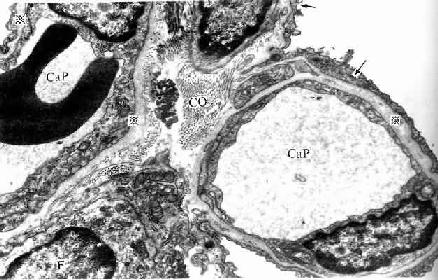

图14-15 人肺泡隔电镜像 ×13500

Cap毛细血管,F成纤维细胞,

CO胶原原纤维,※基膜,↑Ⅰ型肺泡细胞

(上海医科大学电镜室供图)

(2)肺泡隔( alveolar septum):相邻肺泡之间的薄层结缔组织构成肺泡隔,属肺的间质。肺泡隔内含密集的毛细血管网,毛细血管为连续型,内皮甚薄,无孔,胞质内含较多吞饮小泡。隔的厚薄不一,弹性纤维较丰富,也有少量胶原纤维和网状纤维,并有成纤维细胞、巨噬细胞、浆细胞和肥大细胞等以及淋巴管和神经纤维。隔内丰富的弹性纤维有助于保持肺泡的弹性,老年人弹性纤维退化,炎症等病变也可破坏弹性纤维,使肺泡弹性减弱,肺泡渐扩大,导致肺气肿,肺换气功能减低。隔内的毛细血管大多紧贴肺泡上皮,上皮基膜与内皮基膜相互融合;有的部位的肺泡上皮与毛细管内有少量结缔组织(图14-15)。

(4)气血屏障(blood-air barrier):肺泡内气体与血液内气体分子交换所通过的结构称气血屏障。它由以下结构组成:肺泡表面液体层、Ⅰ型肺泡细胞与基膜、薄层结缔组织、毛细血管基膜与内皮。有的部位的肺泡上皮与血管内皮之间无结缔组织,两层基膜直接相贴而融合(图14-15)。气血屏障很薄,总厚度约0.5μm。间质性肺炎时,肺泡隔结缔组织水肿,炎症细胞浸润,以致肺气体交换功能障碍。